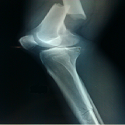

Association très rare: fracture de la diaphyse fémorale associée à une fracture de Hoffa homolatérale

Younes Ouchrif, Issam Elouakili

PAMJ. 2014; 19: 63. Published 23 September 2014